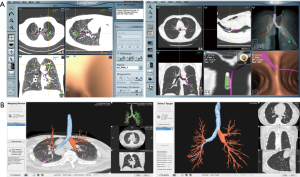

In the United States, there are two EM navigational systems available for clinical use; superDimension (Covidien, Minneapolis, MN, USA, Figure 1) and SPiNView (Veran Medical Technologies, St. Louis, MO, USA, Figure 2). Both systems are based on the same fundamental concept. A CT scan using a dedicated protocol is obtained for planning ENB targets and to overlay the magnetic field to the CT scan and the patient anatomy. The superDimension system (Covidien, Minneapolis, MN, USA) consists of several components. The main processor unit, steerable extended working channel catheter with different tip angulations ranging from 45o to 180o, a locatable guide and the EM board which generates the EM field and lies underneath the patient throughout the procedure. During the pre-procedure planning phase, the target lesion is identified using proprietary software (Figure 3, Figure 4A).

The SPiNView system (Veran Medical Technologies, St. Louis, MO, USA) uses a tracking pad that serves as a reference point, providing feedback information for the system to maintain registration despite the change in location of the target lesion due to respiratory variation. Ideally, to maximize accuracy, CT scan images are obtained during inspiration and expiration for the computer algorithm to compensate for the dynamic respiratory changes. As with the superDimension system, SpinDrive requires a pre-procedure planning phase that is performed using proprietary software loaded onto a dedicated laptop (Figure 3). The main piece of equipment is composed of a central unit with a generator that creates the EM field which projects down, over the patient. Another major difference is in the biopsy instruments. They are always-on tip trackable, eliminating the need for an extended working channel, but limiting the directionality. Because the instruments are tip-tracked, the need for fluoroscopy to ensure appropriate positioning is obviated. The biopsy forceps and brushes are 1.8 mm in outer diameter (OD) and histology and cytology needles are available in 19 and 21 gauge (G) respectively (Figure 4B).